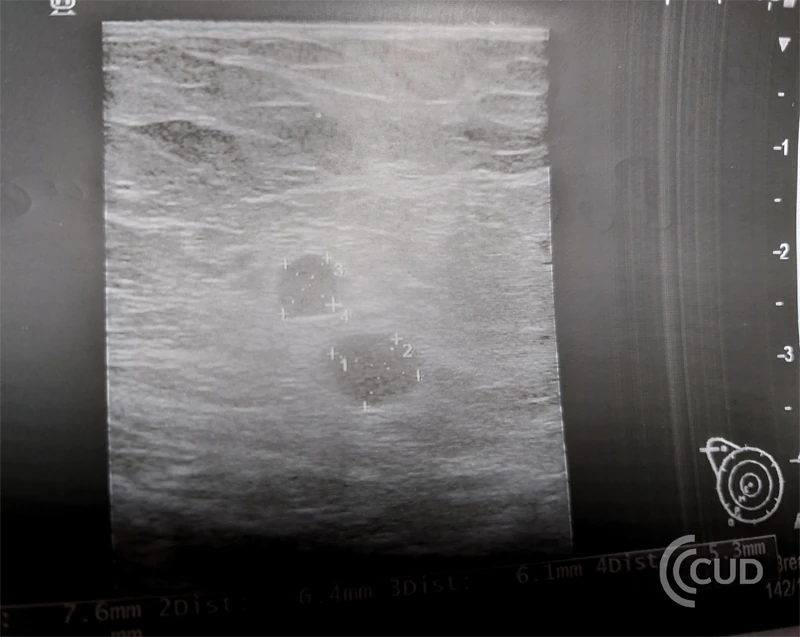

Prawidłowe węzły chłonne są rożnej wielkości i mogą występować praktycznie wszędzie , ale główną ich cechą jest to że są podłużne czyli 2x dłuższe niż grubsze , mają hyperechogeniczną symetryczną wnękę i prawidłowe mają odwnękowe unaczynienie .

W badaniu USG widoczne były liczne nieprawidłowe węzły chłonne, owalne, ciemne bez widocznej wnęki bez widocznego unaczynienia, niektóre miały ogniska martwicy – cechy przewlekłego procesu.

Węzły takie muszą być jak najszybciej zbadanie histopatologiczne, chirurg pobiera cały węzeł i patomorfolog ocenia w badaniu histopatologicznym rodzaj i charakter zmian.